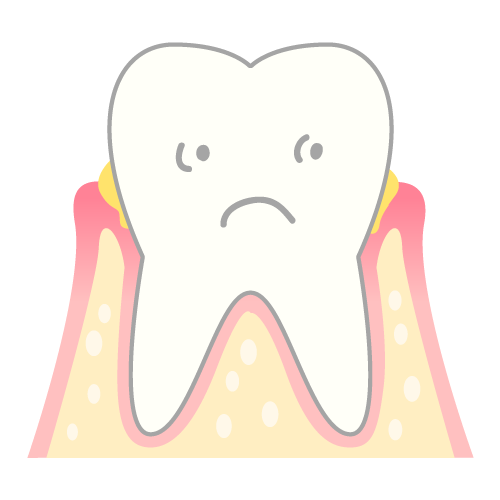

歯周病

歯と歯茎の間の溝(歯周ポケット)に細菌が溜まり炎症を起こす病気です。歯周病菌は、特に悪臭の強いメチルメルカプタンを大量に産生します。 歯科医院での歯周病治療と徹底したセルフケアが有効です。